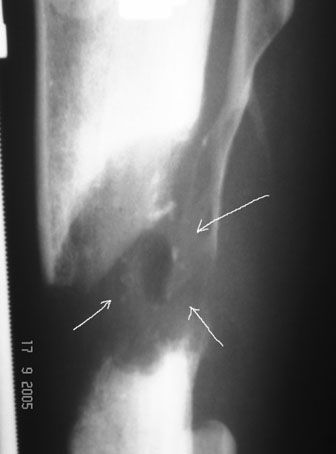

10 дней назад ранка на передней поверхности средней трети голени и по внутренней поверхности нижней трети голени, (по проекции стержня апп.Гофмана) открылись вновь. В настоящий момент отделяемого из обеих ран нет (wound1;2).

Рентгенологически определяется дистракционный регенерат удовлетворительной плотности и наличие в нем полости (now 1;2;3).

После последнего R- снимка 4 дня назад, аппарат переведен в режим фиксации.